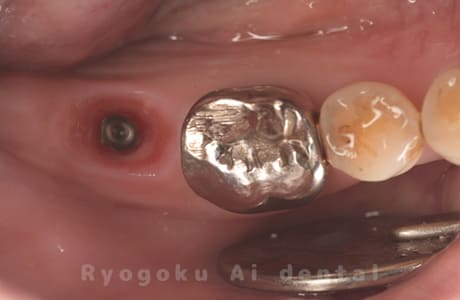

Case07

-

- 原因

- 右下6番歯根破折

- 治療内容

- インプラント治療

- 治療費用

- 約600,000円

右下の腫れが治らないとの事でご来院された患者様です。歯が割れていたため、抜歯を行い、骨に代わるお薬を入れ、インプラントを埋入致しました。経過良好で大変満足していただけました。

<リスク・副作用>

治療後、痛みや違和感、出血、腫れなどが出る事があります。喫煙者、糖尿病などの方の場合、歯が生着しない場合があります。